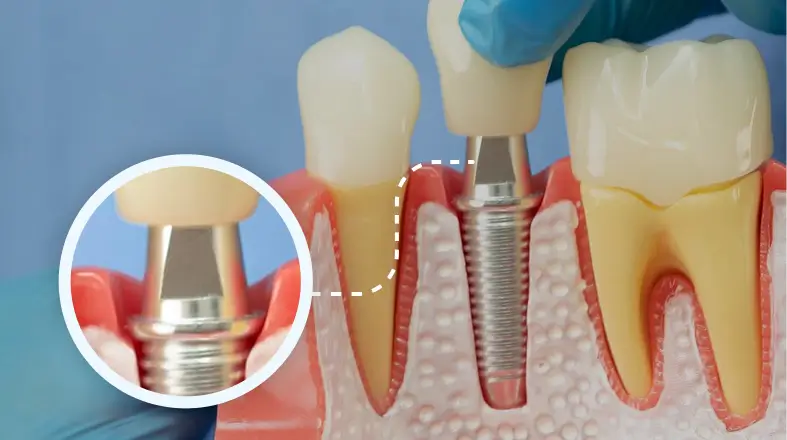

2 Placing the abutment

Made of titanium, gold, or porcelain, this part attaches to the implant and connects it to the crown.

2 Placing the abument

Getting a dental implant requires oral surgery, generally using local anesthesia. Your oral surgeon will cut into your gum to expose the bone. Holes are drilled into the bone where the metal implant will be placed.

After this procedure, you’ll still have a gap where your tooth is missing. Your dentist might be able to fabricate a temporary solution to fill in the gap for cosmetic reasons.